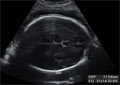

El fémur es el hueso más largo del feto, por eso se utiliza en la estimación de la edad gestacional del bebé. Al ser el hueso más largo, el error de medición se minimiza. En realidad no medimos el hueso en toda su longitud, sino su parte osificada. En la imagen se aprecia con nitidez el hueso, así como la medición, tomada entre dos puntos que se señalan con una cruz.

Ecografía del hueso del fémur en el tercer trimestre de embarazo